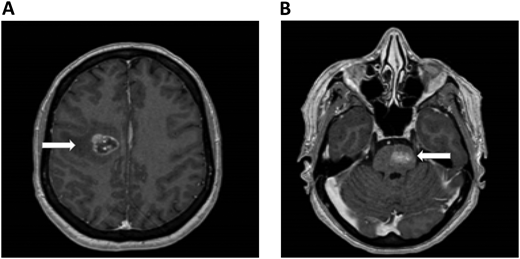

A 61-year-old woman with no prior medical history presented with dizziness and nausea. She was diagnosed with stage IV non–small cell lung cancer (epidermal growth factor receptor exon 17 deletion) with brain metastases and no evidence of ICH (Figure 1). Osimertinib was initiated as first-line therapy. One week after starting osimertinib, she developed right leg edema. Bilateral lower-extremity venous Doppler confirmed a new right calf DVT. Platelets, renal and hepatic function, partial thromboplastin time, and prothrombin time were normal.

Brain MRI in a patient with non–small cell lung cancer and brain metastases. An axial section of a T1 image with contrast shows right frontal metastases (Panel A) and brain stem metastases (Panel B). The white arrows denote these findings.

Hematology was consulted to evaluate whether therapeutic- dose anticoagulation can be given in a patient with newly diagnosed brain metastases. Since her previous brain imaging was 3 weeks earlier, a repeat brain noncontrast CT scan was performed, showing a mild decrease in the size of the brain metastases with no evidence of active bleeding. Her distal DVT was considered to carry a low-intermediate thrombotic risk, potentially enabling reduced-dose anticoagulation if needed. On the other hand, the patient was assessed to have a standard ICH risk, meaning that anticoagulation would likely not lead to a clinically meaningful increase in ICH risk in this setting. Therefore, therapeutic-dose anticoagulation was started with apixaban at 10 mg twice daily for 1 week, followed by 5 mg twice daily. She also continued her anticancer therapy. In this case we did not recommend a routine surveillance brain computed tomography (CT) to assess for ICH after starting anticoagulation.